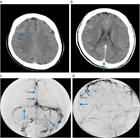

1. 脳静脈血栓症はCTやMRIにて診断を行う。特に、MRIのT2*強調画像Susceptibility-Weighted ImageSWIとMRV(magnetic resonance venography)、あるいはCTV(CT venography)でまず診断を行い、必要に応じて脳血管造影を行うことが推奨される(推奨度1)